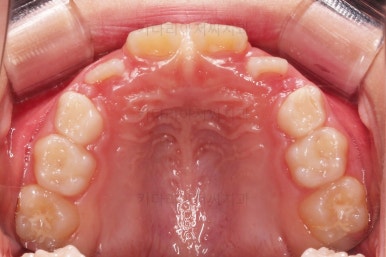

장치 사용 4달째 모습입니다.

벌써 개방교합이 개선되고 있고, 반대교합도 많이 좋아져서 거의 위아래 앞니가 비슷한 위치까지 왔네요.

왼쪽 하단 사진의 어금니에 있는 금속성 장치는 band & loop(밴드 앤 루프)라고 하는 공간유지장치인데요. 오래 써야하는 유치가 일찍 빠지는 바람에 그 공간을 잡아두는 장치입니다.